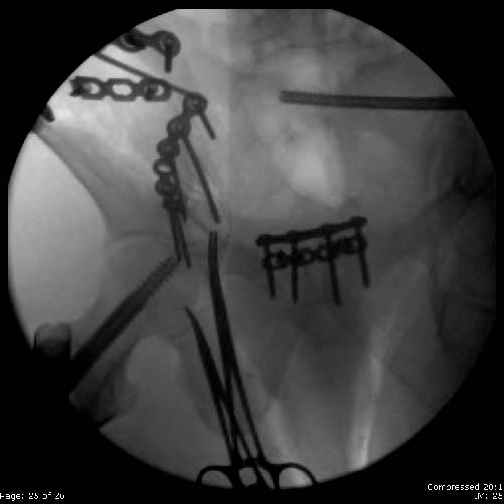

Here are the postop fluoros.

First exposed symphysis & clamped w/Faraboeuf as close to anatomic as possible.

Then extended to R ilioinguinal,really just the lateral window.

Reduced the triangular wedge piece of iliac wing to posterior intact ilium (crescent), held w/k-wire, then used 3-hole push plate to keep from moving, lagged from lat-med w 3.5 screw.

Then 6-hole plate along brim with 1 screw in R sacral ala. Then lagged 2 screws along crest A --> P. finally 10-hole plate along inner aspect of crest. R posterior ilium still a bit stepped off.

Symphysis then 'fine-tuned' & reduced as close as possible to anatomic (but, still with forward rotation of R hemipelvis - or, is it extension?) Accepted that amount of deformity and plated symph

with 4-hole symphyseal plate.

Fluoroed L SI joint and it seemed stable, but wide. So, applied c-clamp to try to squeeze down L SI joint (and note, on the last slide attached, that it's still wide), and got it closer. Single perc Iliosacral screw 40mm thread.

Applied second plate anteriorly on symphysis as I wasn't confident L SI was as stable as it could be and wanted to protect it better.